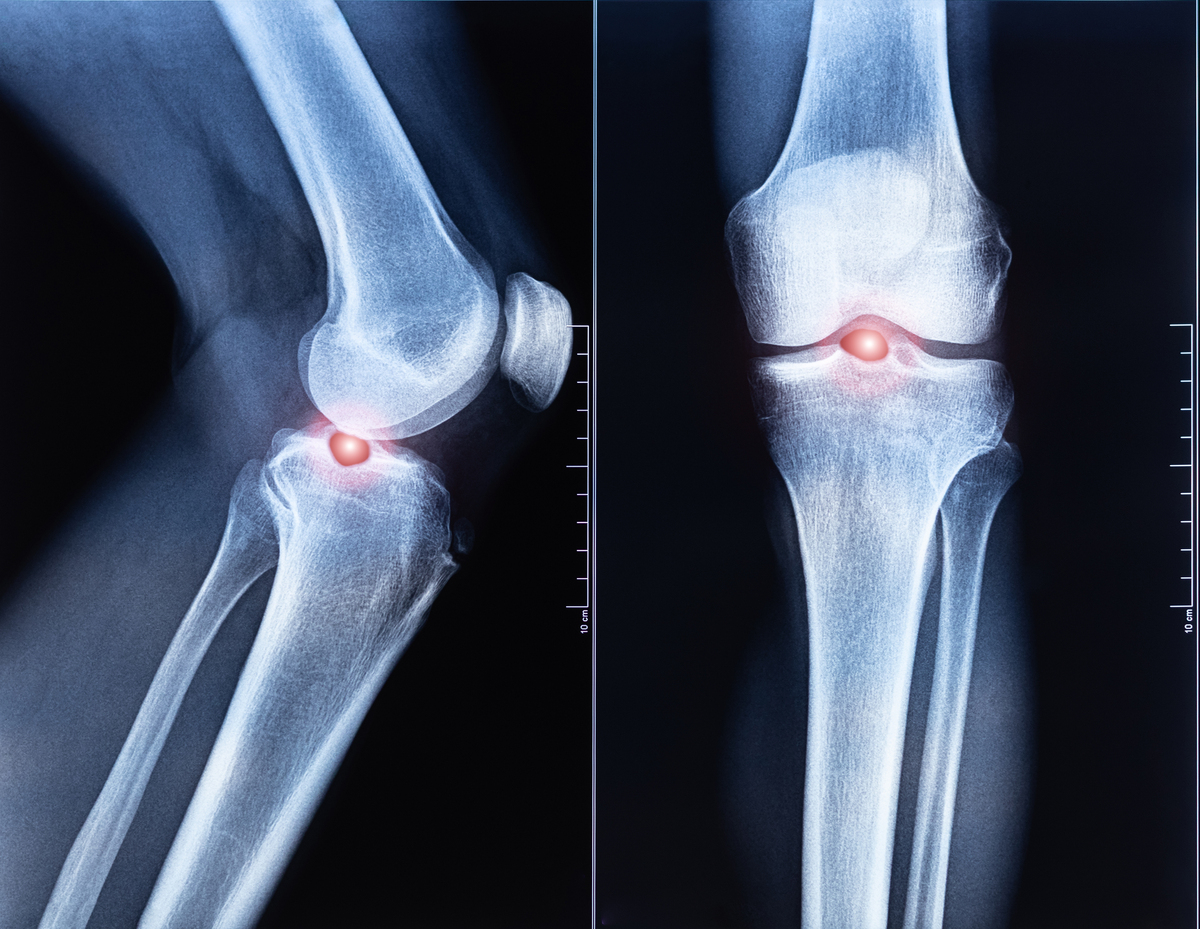

膝关节骨性关节炎是一种慢性炎症性疾病,主要表现为膝关节的疼痛、僵硬和功能受限。它是由于膝关节软骨的退化和变性引起的,导致骨头之间的摩擦和磨损,最终导致关节炎的发生。该疾病主要发生于老年人,但也可能影响年轻人,如运动员和受伤者。治疗方法包括药物治疗、物理治疗、手术治疗和辅助治疗等。